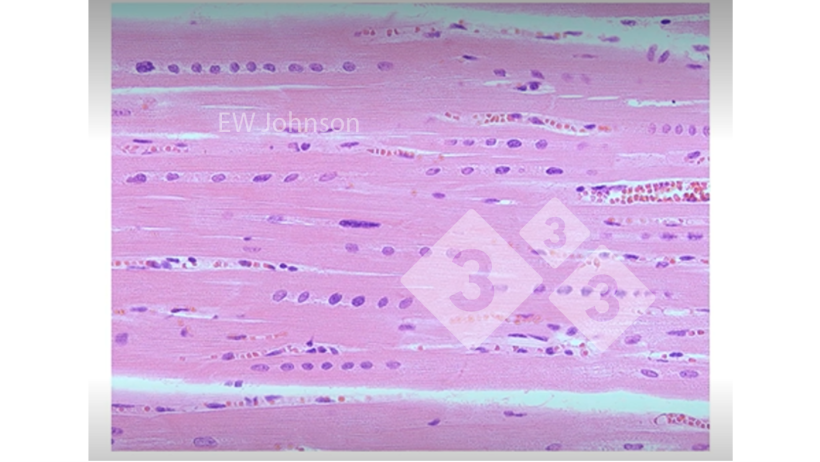

Por vezes podemos encontrar coisas que não esperávamos ver (figura 3).

Figura 3. Músculo cardíaco com hemorragia, necrose hialina e alinhamento dos núcleos mostrando deficiência de vitamina E e selénio. Estes porcos não teriam um sistema imunitário que funcionasse normalmente.